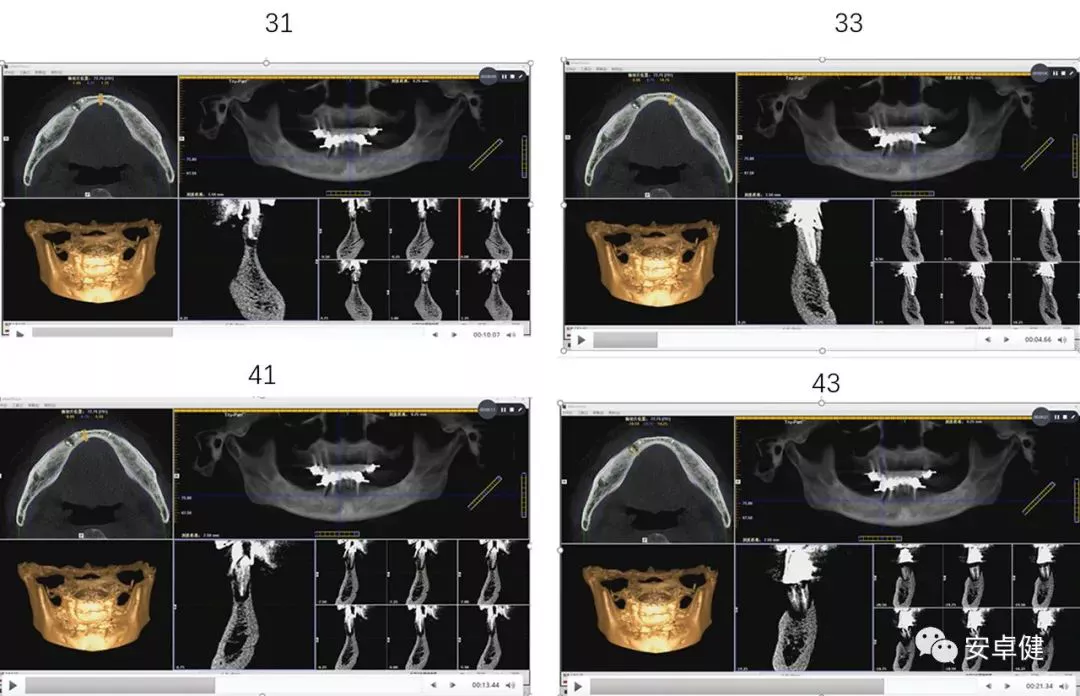

术后即刻CBCT示种植体三维植入位置良好,唇舌侧骨板可

二期复诊CBCT影像学检查示种植体周围骨密度良好,骨量可

种植两年后复诊CBCT影像学检查示种植体周围骨密度良好

▷ 影像学检查

• 可见11、12、13、14、15、21、22、23、24、31、33、44、43、42、41根管内高密度影及上部烤瓷桥修复体;

• 31、33、41、42、43、44可见根尖及周围低密度暗影。

术前CBCT影像学检查